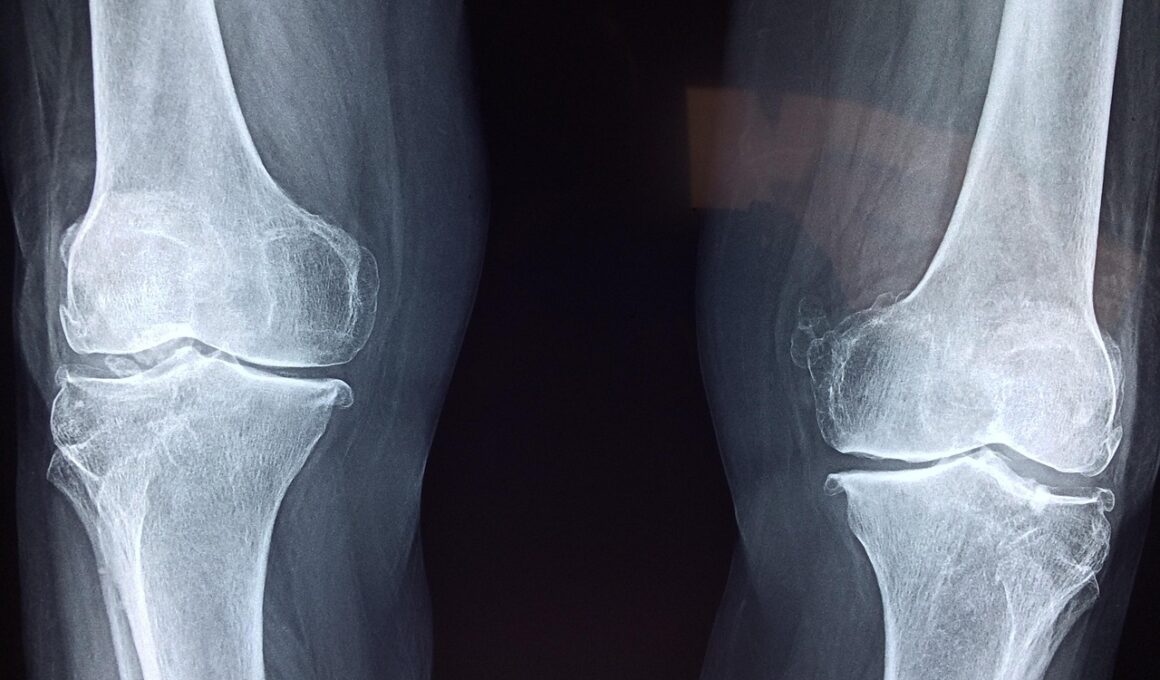

Many people suffer from chronic joint problems that can be influenced by hydration levels. Joint diseases such as osteoarthritis and rheumatoid arthritis can benefit from adequate hydration, emphasizing its importance in managing these conditions. Hydration supports the production of synovial fluid, which is essential for cushioning joints and enhancing mobility. For individuals with arthritis, staying hydrated can alleviate the pain associated with dry joints, which typically results from insufficient lubrication. Medical professionals often recommend increasing water intake in patients diagnosed with chronic joint conditions. Ensuring correct hydration can help reduce inflammation and improve joint function significantly. Furthermore, proper hydration can aid in the management of weight, decreasing the stress placed on joints. Maintaining a healthy weight directly correlates with less joint wear and tear. Arthritis sufferers have reported improvements in joint stiffness and overall comfort by adhering to hydration recommendations. Therefore, it is critical for individuals with chronic joint conditions to prioritize hydration as a cornerstone of an effective management plan. Thoughtful hydration can lead to enhanced quality of life by improving joint function and reducing pain in daily activities.